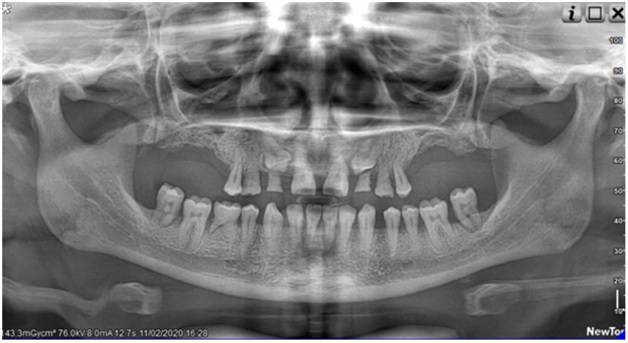

Negli ultimi anni, la TAC Cone Beam (CBCT) è diventata lo standard diagnostico per la pianificazione implantare. Questa tecnologia consente di ottenere immagini tridimensionali ad alta risoluzione delle strutture anatomiche del paziente, permettendo ai clinici di valutare con precisione millimetrica la densità ossea, l’anatomia dei nervi e dei seni mascellari, e di pianificare l’inserimento degli impianti con una accuratezza impossibile fino a pochi anni fa.

La pianificazione digitale consente di simulare virtualmente l’intero intervento prima ancora di toccare il paziente. Software avanzati permettono di valutare diverse opzioni protesiche, di ottimizzare la posizione degli impianti in base alla futura protesi, e di identificare preventivamente eventuali criticità anatomiche.